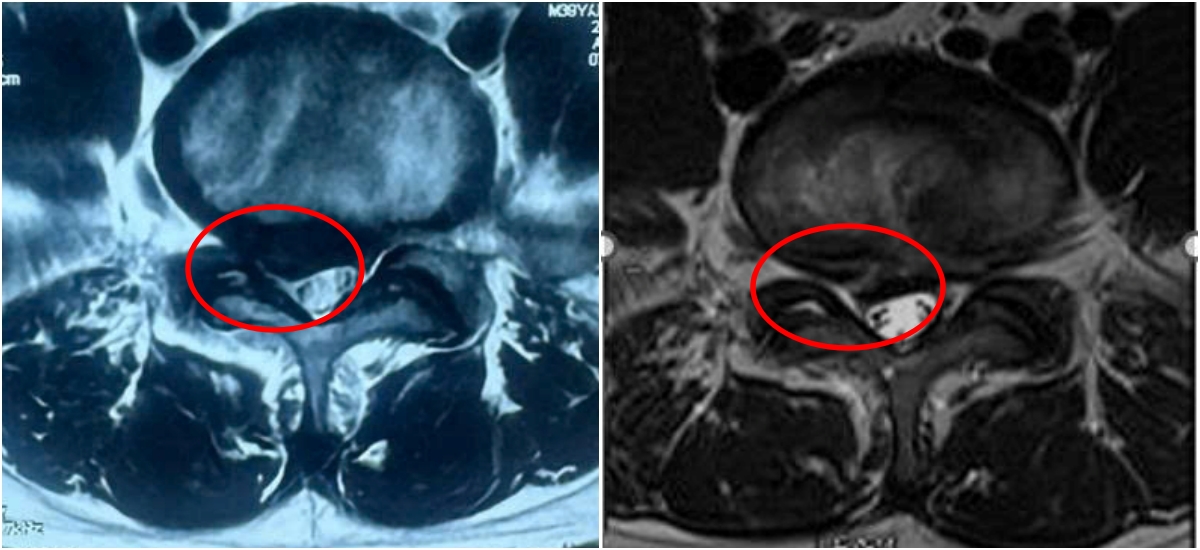

The herniated mass (right) shrinks after radiofrequency ablation compared to before the intervention (left). *Photo: Tam Anh General Hospital*

Following the RFA, Anh Hieu experienced significant pain reduction within the first month. By the second and third months, his pain had nearly disappeared, enabling him to resume normal walking. A follow-up examination three months after the procedure confirmed that the herniated mass had partially retracted, showing no distinct signs of nerve root compression.